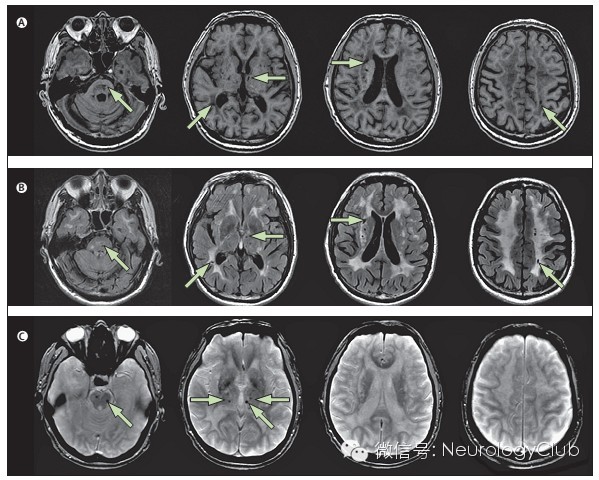

★ 常见腔隙性脑梗死、脑白质疏松和微出血

★ 在MRI的T2像表现为大小不一的高信号,不累及弓状纤维,主要位于侧脑室周围和深部白质。以额叶白质最常受累,其次为颞叶和顶叶,而枕叶受损程度相对较轻。

★ 外囊、颞极的对称性异常信号对诊断有高度提示作用。

★ 微出血部位由多到少依次为皮质和皮质下白质、脑干、丘脑、基底节和小脑

(A 腔隙性脑梗死 B 脑白质病变 C 微出血)